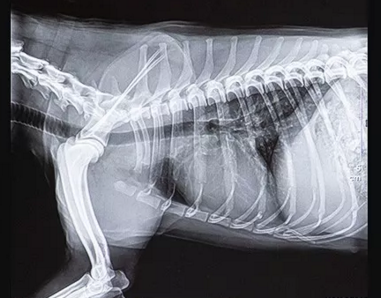

寵物dr拍攝效果

寵物dr拍攝效果圖